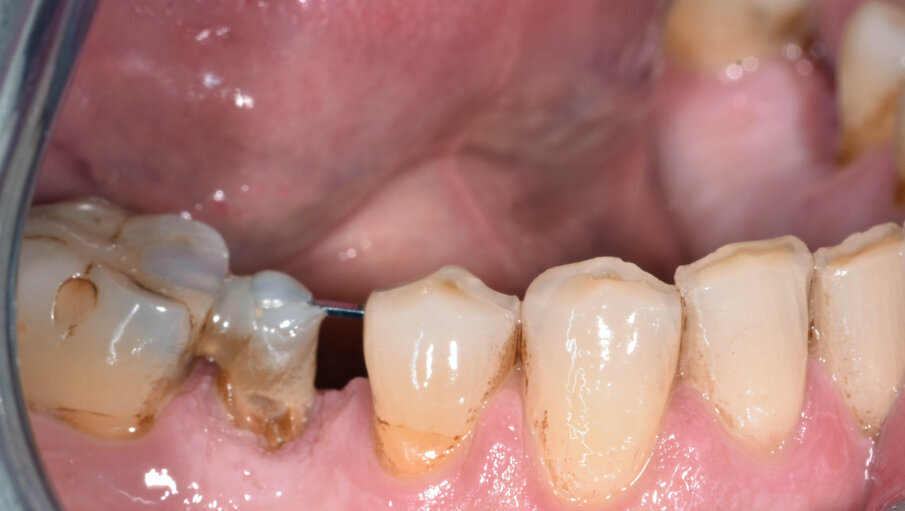

L’estrusione completa del frammento ha richiesto un tempo di 6 mesi, durante i quali è stata modificata più volte l’inclinazione della molla per evitare che il movimento diventasse ortogonale al segmento e mantenere la traiettoria prevista. Così facendo, è stato possibile rigenerare naturalmente l’intero alveolo e inserire, dopo 3 mesi di ulteriore maturazione del tessuto, in un contesto osseo ideale e perfettamente rigenerato un impianto Syra (Sweden & Martina) di diametro 4.25 mm e lungo 11 mm.

Dopo 3 mesi dall’inserimento implantare è stato possibile prendere un’impronta e di precisione e realizzare una corona singola avvitata.